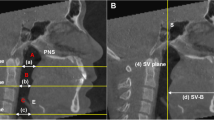

The oropharynx in CBCT was defined as the region from the plane passing the posterior nasal spine to the plane passing the tip of the epiglottis [17]. The volume and the most constricted axial (MCA) area of the oropharynx were calculated (Fig. 1A). Airway segmentation threshold values ranging from 50 to 70 were adjusted to discriminate soft tissue from the airway. As shown in Fig. 1C and D, the anterior-posterior (AP) diameter, lateral diameter, and ratio of AP/lateral diameter were also measured at the level of the PNS plane and the tip of the epiglottis (E) to analyse the morphology of the oropharyngeal airway.

Measurements of oropharynx size and hyoid bone position. A Volume and most constricted axial (MCA) area of the oropharynx. B Five hyoid bone measurements: H-Eb (1), H-C3 (2), H-Me (3), H-X (4), and H-Y (5). C Anterior-posterior (6) and lateral (7) diameters of the oropharynx at the level of the PNS plane. D Anterior-posterior (8) and lateral (9) diameters of the oropharynx at the level of the epiglottis tip

Hyoid measurement

As shown in Fig. 1B, five linear parameters were selected to measure the hyoid bone position: H-Eb (highest point of hyoid bone to the epiglottis base); H-C3 (highest point of hyoid bone to the most anterior and inferior point of the third cervical vertebra); H-Me (highest point of hyoid bone to the menton); H-X (perpendicular distance from the highest point of hyoid bone to the vertical line passing through the sella); and H-Y (perpendicular distance from the highest point of hyoid bone to the horizontal line passing through the sella).